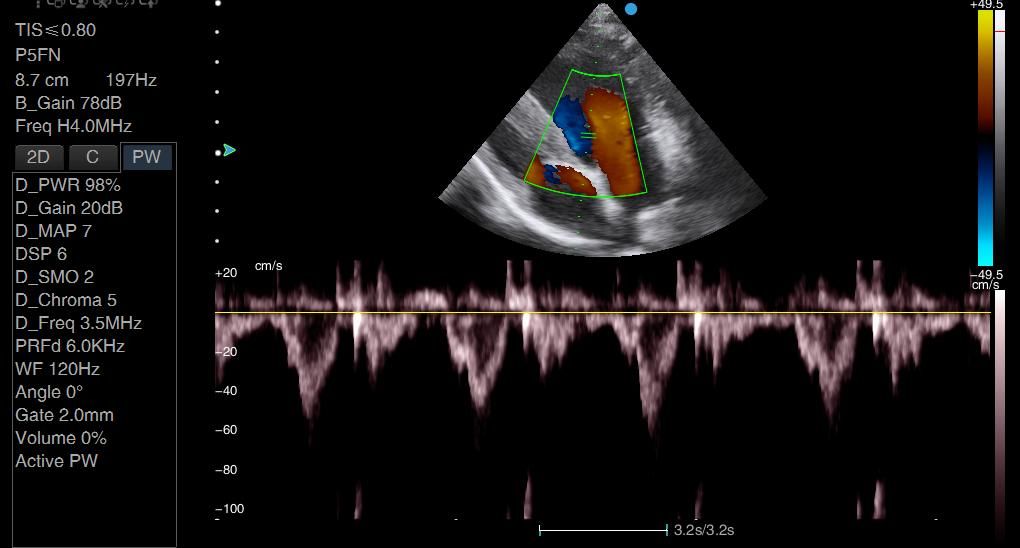

I think the image quality is great and what this machine really excels at is colour, Doppler.

Many machines I've tried the cardiac Doppler functions are just not up to scratch - it is really difficult to assess for turbulence, for example around mitral valves, but also in the abdomen because some machines just slow the frame rate so much that it's impossible to use colour Doppler effectively.

The Apogee 2300V absolutely excels and has really great resolution on its colour Doppler. So if you're interested in cardiac scanning, this is a really good machine to go for.

Images from the Apogee 2300V